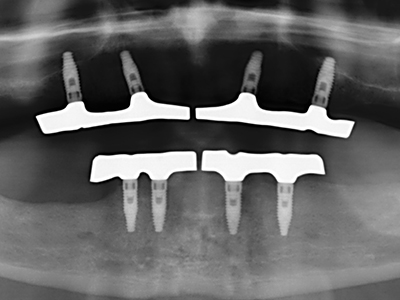

As shown in the past, basically any bone surgery procedure represents a possible indication for piezosurgery. Thus preparation of the mobile segment in distraction osteogenesis (Fig. 23-25) and sandwich osteotomy uses special attachments without endangering the blood supply to the crestal section, which is essential for the success of both techniques (Gonzalez-Garcia, Diniz-Freitas et al. 2008).